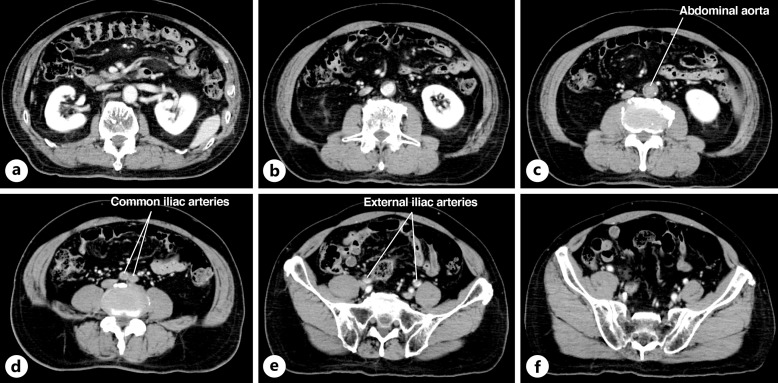

Case presentation: An 83-year-old man presented at our emergency department with a complaint of sudden-onset paraparesis. Initially, spinal cord infarction was suspected due to clinical course and neurological findings, but thoracolumbar MRI showed normal findings. On admission, symptoms associated with aortoiliac occlusion were not present, except for muscle atrophy in the thigh. CT angiography revealed aortoiliac occlusion, leading to a diagnosis of Leriche syndrome.